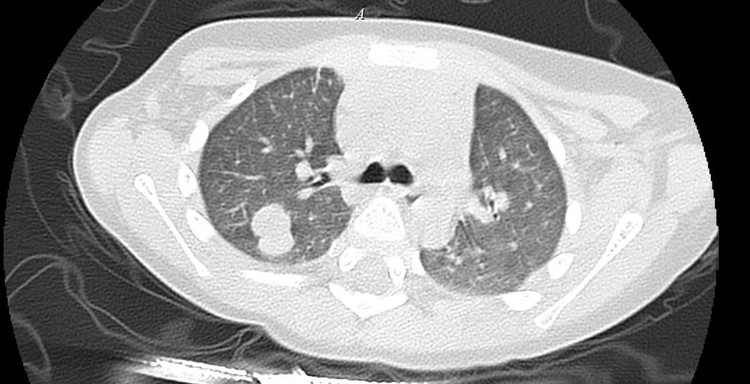

Kết quả xét nghiệm của bệnh nhi - Ảnh BVCC

Nếu nam giới bị tinh hoàn ẩn ở cả hai bên, nguy cơ vô sinh sẽ rất cao. Kết quả xét nghiệm dịch tinh đồ của họ thường không có tinh trùng. Một số người bệnh còn không thể quan hệ tình dục được do nội tiết tố bị thiếu hụt trầm trọng. Nam giới bị tinh hoàn ẩn thường phối hợp với những dị tật bẩm sinh khác.